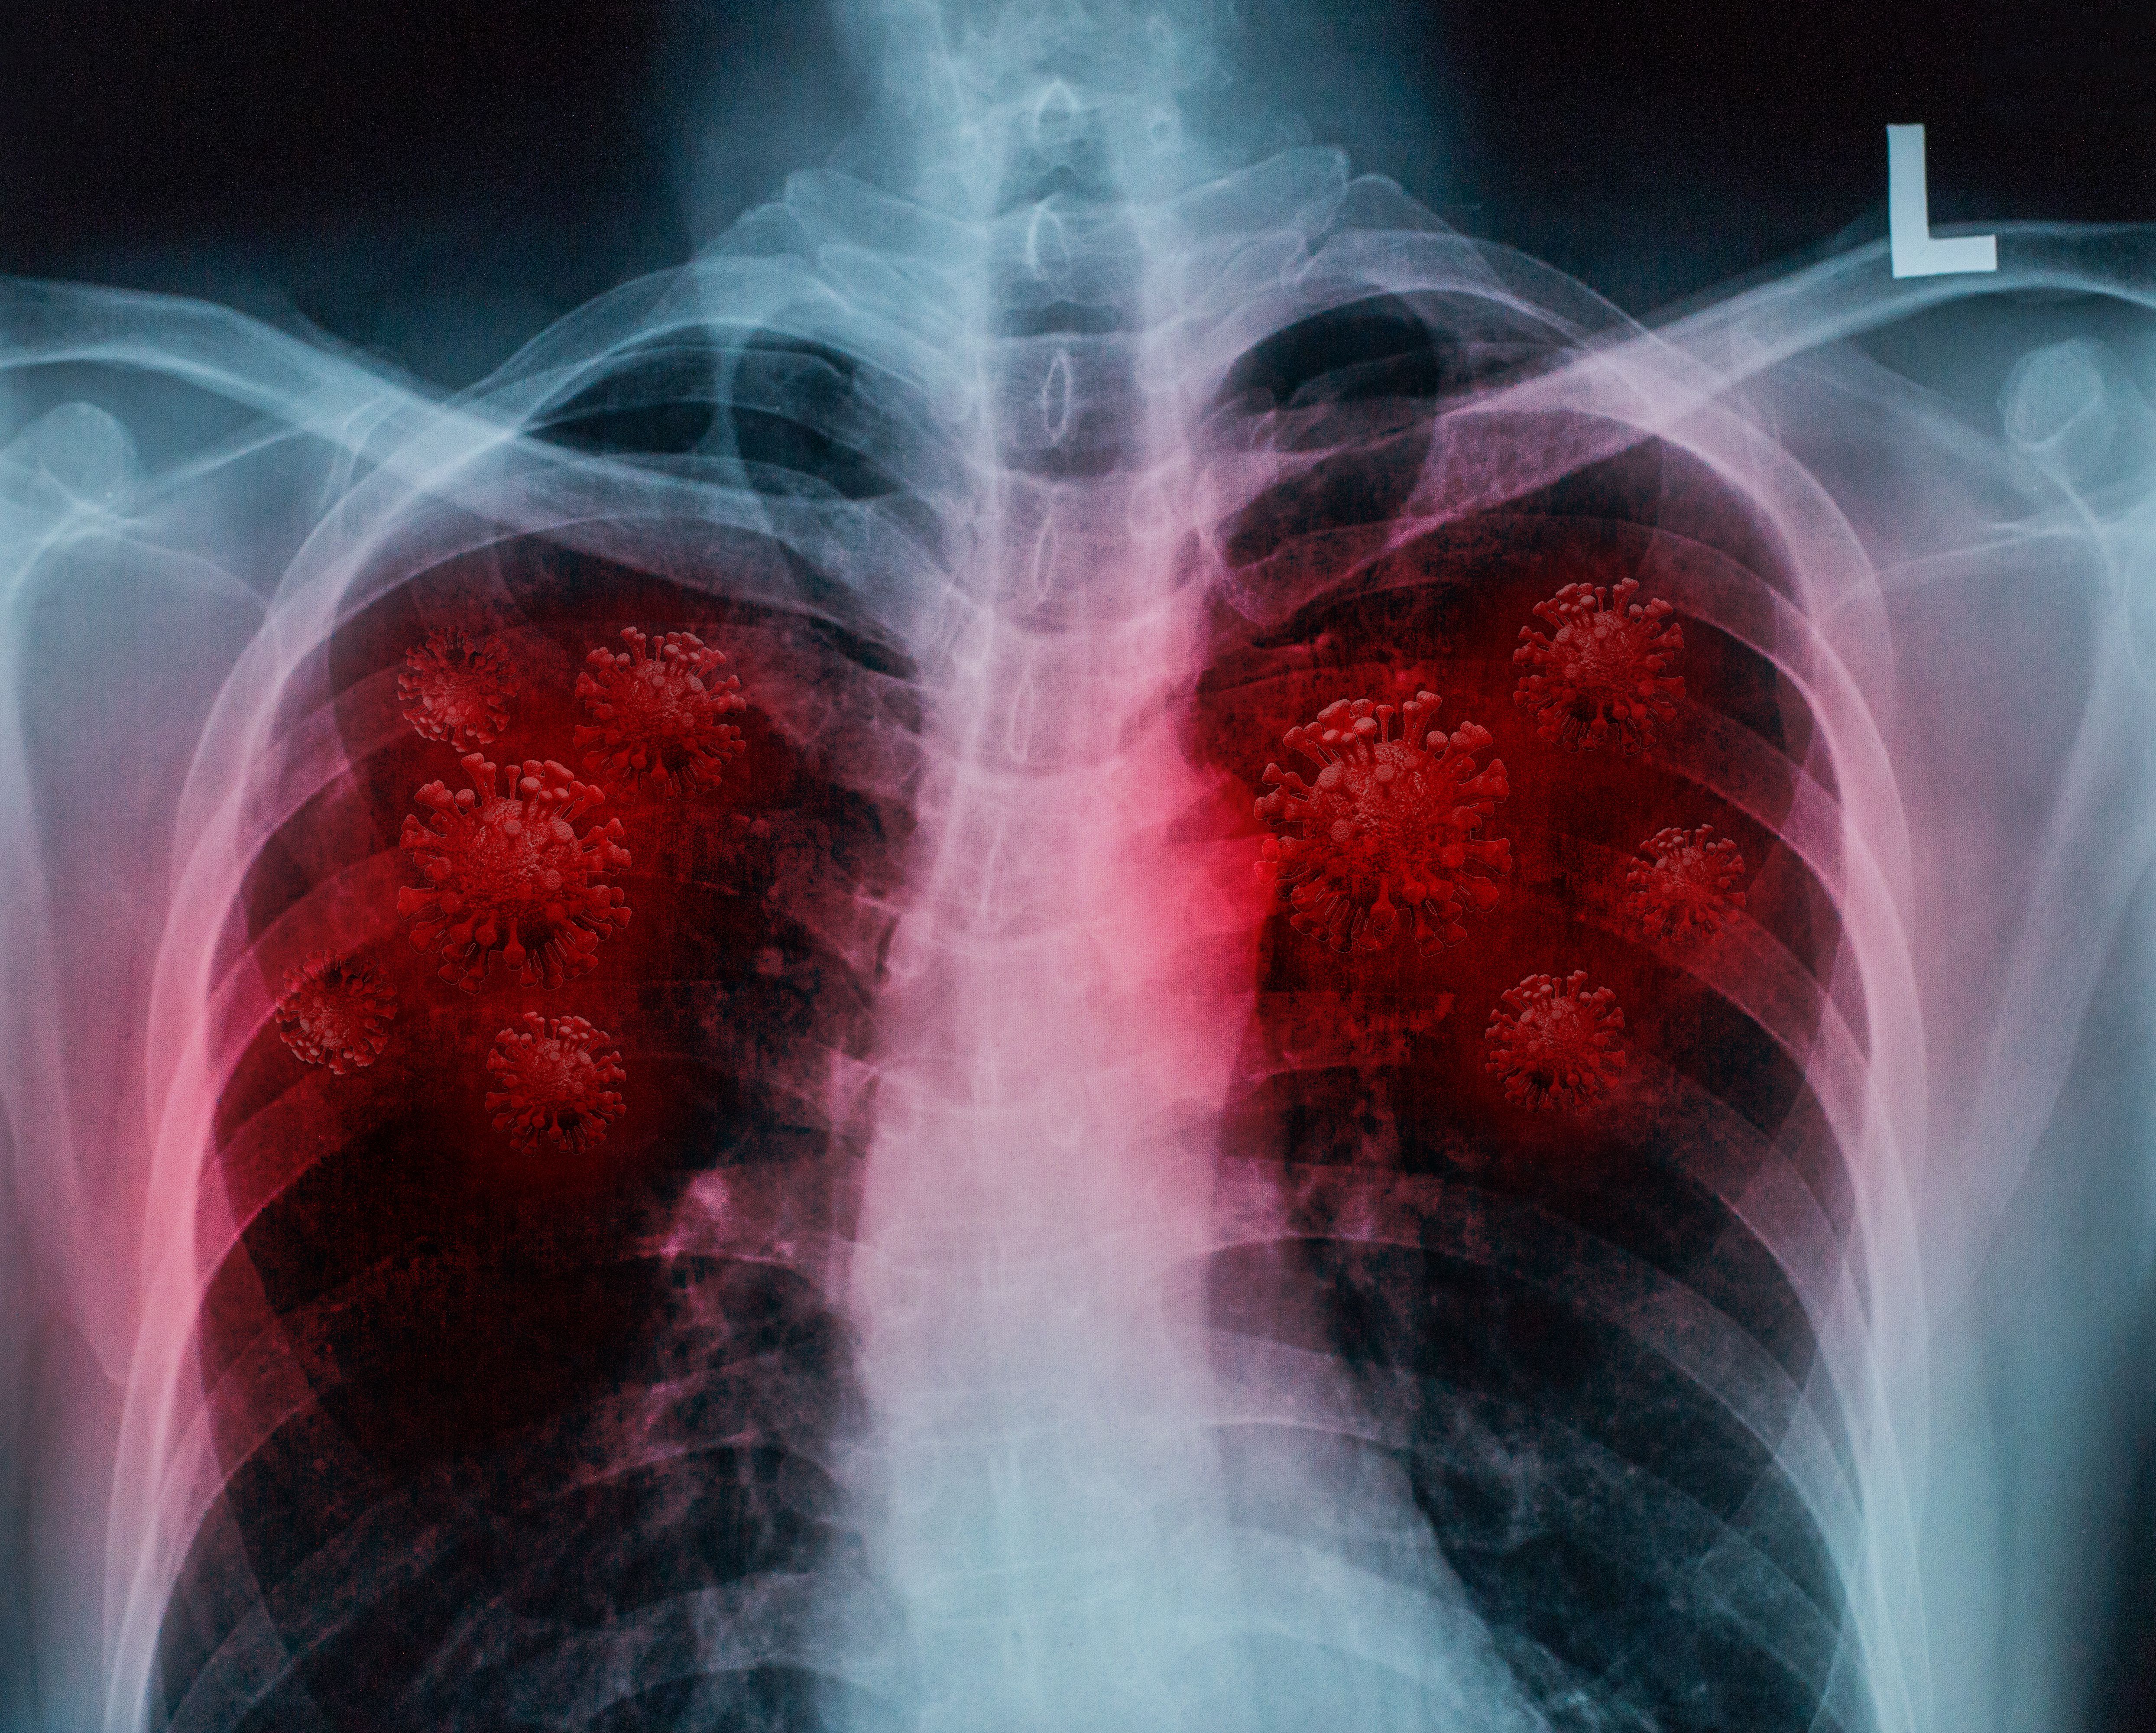

Investigators identify 11 crucial “protection-defining genes” that prevent a severe disease response to COVID-19 infection.

One of the greatest mysteries surrounding COVID-19 is illness severity. Why do some people experience debilitating long COVID or even fatal infection while others are asymptomatic? Advanced age is o… [+3199 chars]